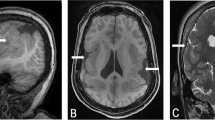

Here, we report a consanguineous family composed of healthy parents and three children, two of whom present Kartagener syndrome (Figure 1). All known genes were excluded as the cause of the laterality defect by linkage analysis, and no deletions or amplifications greater than 1 Mb were identified by array CGH. Genome wide SNP and STRP screening for homozygosity allowed us to identify novel linked regions, providing the basis for the identification of a new gene for Kartagener syndrome.

Family AC-79 is composed of five individuals. The parents and one of the children (II-1) are unaffected, whereas the two other children (II-2 and II-3) are affected. The parents are consanguineous, as shown in the pedigree (Figure 1). Individual II-2 has dextrocardia with concordant atrioventricular and ventriculoarterial connections (inverted normal heart {I,L,I}, according to Van Praagh R segmental approach to diagnosis). He has no cardiac defect. Individual II-3 has a complex congenital heart disease with dextrocardia, situs inversus of the atria, persistence of the right and left superior vena cava with absent innominate vein, an unroof coronary sinus, an atrial septal defect, discordant atrioventricular connection with congenitally corrected transposition of the great arteries (or {I,D,D}, physiologically corrected transposition of the great arteries, according to Van Praagh R segmental approach to diagnosis), pulmonary atresia, and a large ventricular septal defect. He also has decreased mucociliary transport and chronic respiratory disease. He had a right and a left Blalock–Taussig shunt performed.

Nasal biopsies were taken for individuals II-2 and II-3 in order to diagnose Kartagener syndrome. Ciliary ultrastructure was normal in both biopsies. Ciliary ultrastructure and beat frequency were also analysed after cell culture. For individual II-2, the outer and inner dynein arms were absent after ciliogenesis and the cilia were immotile or did not present a coordinated movement. The same result was observed in a second nasal biopsy. For individual II-3, the ciliary culture did not show any ultrastructural abnormality. However, the cilia were immotile. Based on the clinical features, and the ciliary functional and ultrastructural analysis for individuals II-2 and II-3, both were considered to be affected with the Kartagener syndrome.